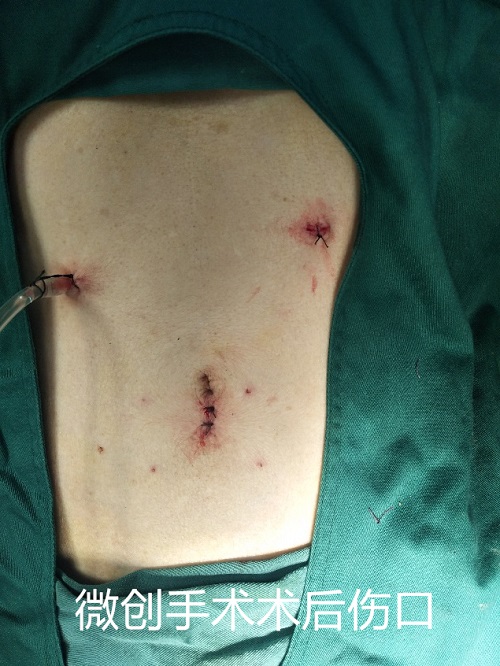

在龙川县中医院多学科联合精准治疗下,且得益于腹腔镜手术创伤小、恢复快、探查彻底的优点,患者逐日康复,出院时体重已回升至41公斤。